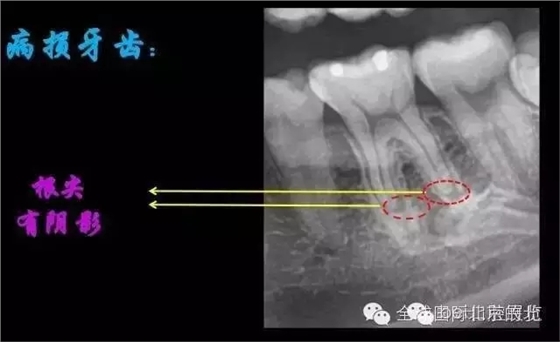

我們再來看看患牙:

X-RAY示:近遠中牙根都有陰影存在,牙周膜都有些許增寬,近中頸部位置牙體有低密度減低影,就是楔狀缺損的位置。 病因分析:楔狀缺損的深齲致牙髓壞死引起的根尖炎癥,應囑患者以后改變刷牙方式 診斷:36慢性根尖炎急性發(fā)作 治療方案:36做根管治療,然后充填完成后行冠修復。 首次治療過程:開髓引流,無明顯滲出液,pathfile疏通根管,沖洗,氫氧化鈣暫封,一周復查。